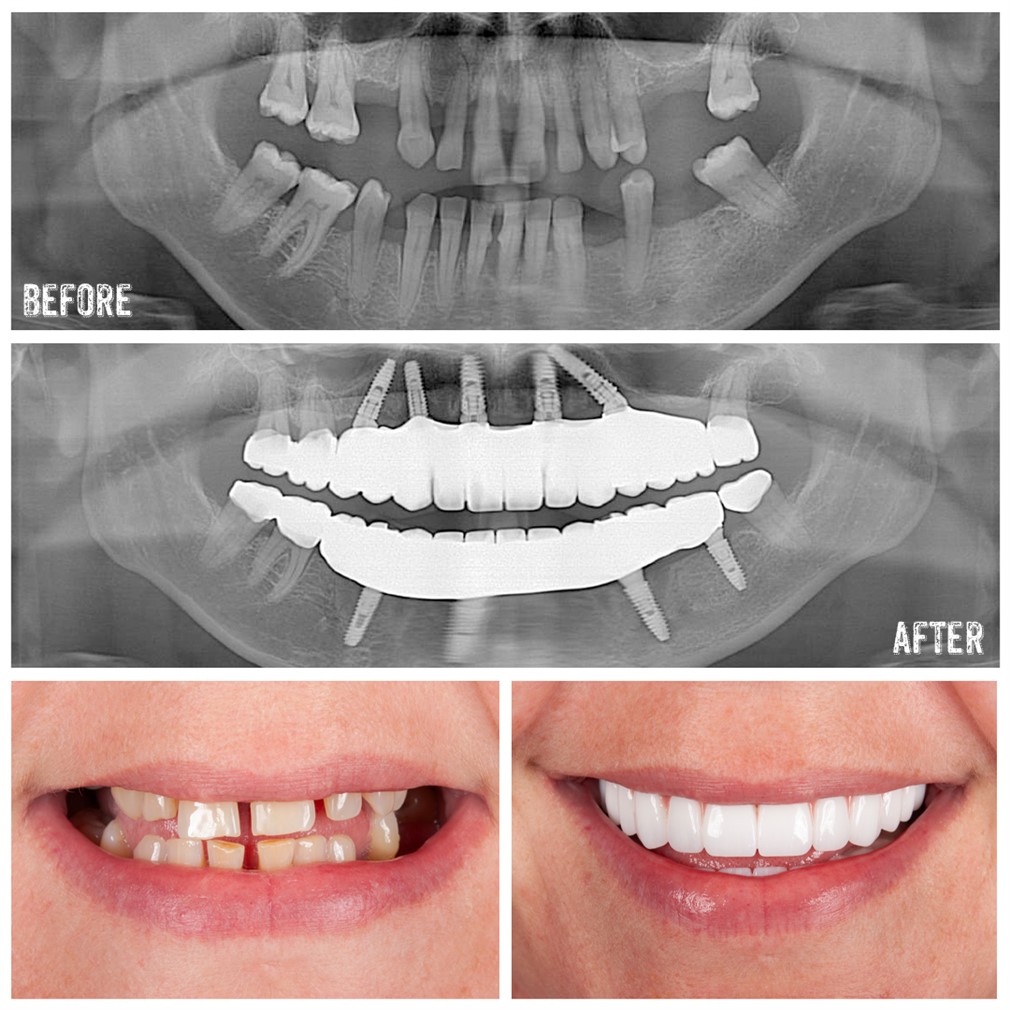

Yes, you can still get a dental implant 10 years after a tooth extraction, but if the bone has deteriorated, a bone graft may be required to create a stable foundation for the implant.